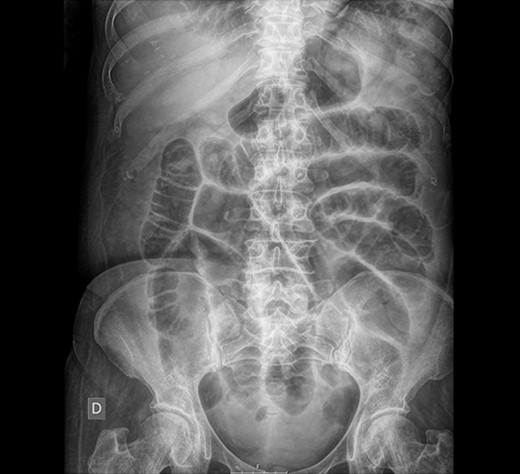

Abdominal X-ray: generalized dilatation of the small intestine without distal air in the colon or the rectum.